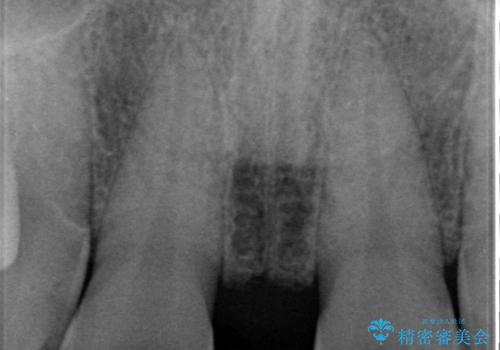

- 前歯部のすきっぱと歯並びが気になるので診て欲しいといらっしゃった方の症例です。

全顎矯正は御希望されなかったため、上顎前歯部のみの部分矯正とオールセラミッククラウンによる補綴を行いました。